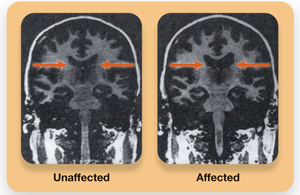

Brain Differences: Enlarged ventricles, reduced frontal cortex activity, increased dopamine (DA) activity (positive symptoms), and underactive glutamate (GLU) systems (negative symptoms) are observed.